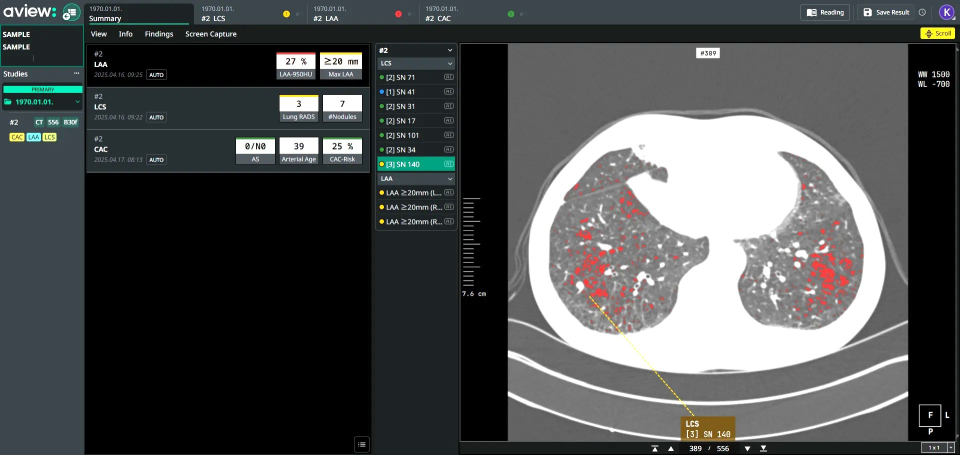

The three AVIEW chest products introduced by Coreline Soft are specialized for diagnosing chronic obstructive pulmonary disease (COPD), lung cancer and nodule detection (LCS), and interstitial lung disease (ILD). They feature automatic analysis based on low-dose chest CT scans and provide quantitative assessment functions. A representative from Coreline Soft stated, “We have maintained ongoing research collaborations with Boramae Medical Center, and after thorough verification of effectiveness in real clinical environments and data integration structures, we have decided to proceed with full-scale deployment. We also anticipate future joint academic achievements through diagnostics, multi-disciplinary research, and publications.”